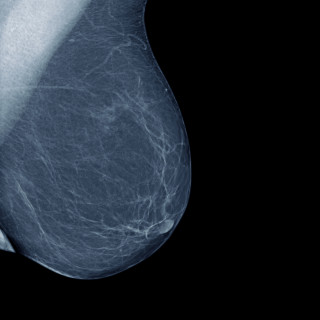

Åreknuter i bena er et vanlig helseproblem med en prevalens på over 20 % i den voksne befolkningen. Årsaken er svikt i klaffefunksjonen i det overflatiske, og eventuelt det dype, venesystemet (1). Klaffesvikten fører til refluks og økt trykk i det overflatiske venesystemet, med påfølgende dilatasjon og forlengelse av venen og åreknuter. Pasientene beskriver plager som smerte, tyngdefornemmelse, kløe, leggkramper og trette ben. Kronisk venøs svikt kan lede til delvis irreversible forandringer som eksem, pigmentering og sårdannelse. Kjønn, overvekt, antall graviditeter, alder, arv og etnisitet...